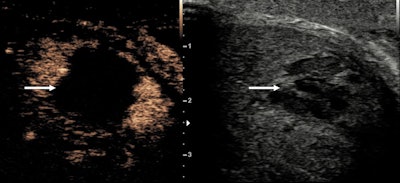

The authors recommend a split-screen approach, with B-mode and CEUS images displayed side-by-side, allowing low mechanical index (MI) B-mode images to localize the area of interest, and they propose a dose of 4.8 ml of SonoVue/Lumason. A CEUS examination requires intravenous access for contrast administration, with a minimum calibre of 18-22-G, and prompt access to resuscitation equipment should be available.

"The B-mode appearance of a penile hematoma can vary with its age, being hyperechoic in the acute phase and cystic with septations in chronic stages. In the long-term, fibrosis can be developed, appearing as an ill-defined echogenic abnormality," the authors noted, adding that on CEUS, a penile hematoma appears as a non-enhancing area, and it allows a confident diagnosis and a better delineation of the hematoma.